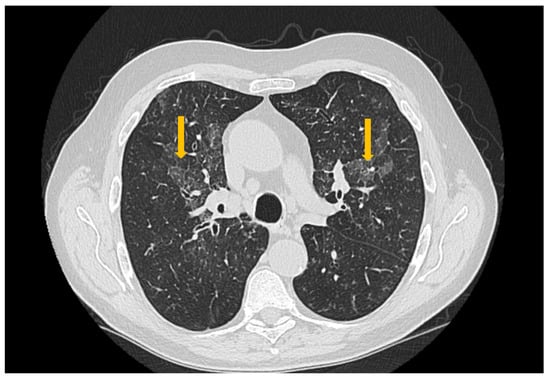

The Role of Imaging Techniques in the Evaluation of Extraglandular Manifestations in Patients with Sjögren’s Syndrome

Sjögren’s syndrome is a chronic autoimmune disease marked by lymphocytic infiltration of the exocrine glands and the development of sicca symptoms, yet some patients also develop extraglandular involvement. Imaging has become relevant for describing these systemic features and supporting clinical assessment. This review discusses the roles of ultrasonography, elastography, computed tomography, and magnetic resonance imaging in evaluating multisystem disease associated with Sjögren’s syndrome. Ultrasonography and elastography help assess muscular involvement by showing changes in echogenicity and stiffness that reflect inflammation and later tissue remodeling. In joints, ultrasound can detect synovitis, tenosynovitis, and early erosive changes, including abnormalities not yet evident on examination. Pulmonary disease, most often with interstitial lung involvement, is best evaluated with high-resolution computed tomography, which remains the most reliable imaging modality for distinguishing interstitial patterns. Magnetic resonance imaging is valuable in assessing neurological complications. It can reveal ischemic and demyelinating lesions, neuromyelitis optica spectrum features, or pseudotumoral appearances. Imaging is also essential for detecting lymphoproliferative complications, for which ultrasound and magnetic resonance imaging can reveal characteristic structural and diffusion-weighted imaging findings. When combined with clinical and laboratory information, these imaging methods improve early recognition of systemic involvement and support accurate monitoring of disease progression in Sjögren’s syndrome. Full article